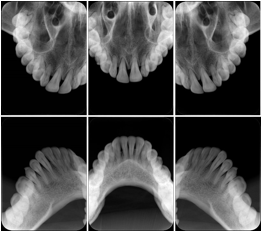

3 Occlusal Vertical Maxilla A Dental Image Layout

DL-C005A

Reference: DL-C005A-U1L0

Reference: DL-C005A-U2L0

00

Occlusal

18, 17, 16, 15, 14, 13, 12, 11, 13, 12, 11, 21, 22, 23

01

17, 16, 15, 14, 13, 12, 11, 13, 12, 11, 21, 22, 23, 24, 25, 26, 27

02

13, 12, 11, 13, 12, 11, 21, 22, 23, 24, 25, 26, 27, 28

3 Occlusal Vertical Mandible A Dental Image Layout

DL-C006A

Reference: DL-C006A-U0L1

Reference: DL-C006A-U0L2

10

48, 48, 47, 46, 45, 44, 43, 42, 41, 31, 32, 33

11

48, 48, 47, 46, 45, 44, 43, 42, 41, 31, 32, 33, 34, 35, 36, 37, 38

12

43, 42, 41, 31, 32, 33, 34, 35, 36, 37, 38

6 Occlusal Vertical A Dental Image Layout

DL-C007A

Reference: DL-C007-U1L1

Reference: DL-C007-U1L2

Reference: DL-C007-U2L1

Reference: DL-C007-U2L2

18, 17, 16, 15, 14, 13, 12, 11

16, 15, 14, 13, 12, 11, 13, 12, 11, 21, 22, 23, 24, 25, 26

21, 22, 23, 24, 25, 26,27, 28

48, 48, 47, 46, 45, 44, 43, 42, 41

48, 48, 47, 46, 45, 44, 43, 42, 41, 48, 48, 47, 46, 45, 44, 43, 42, 41